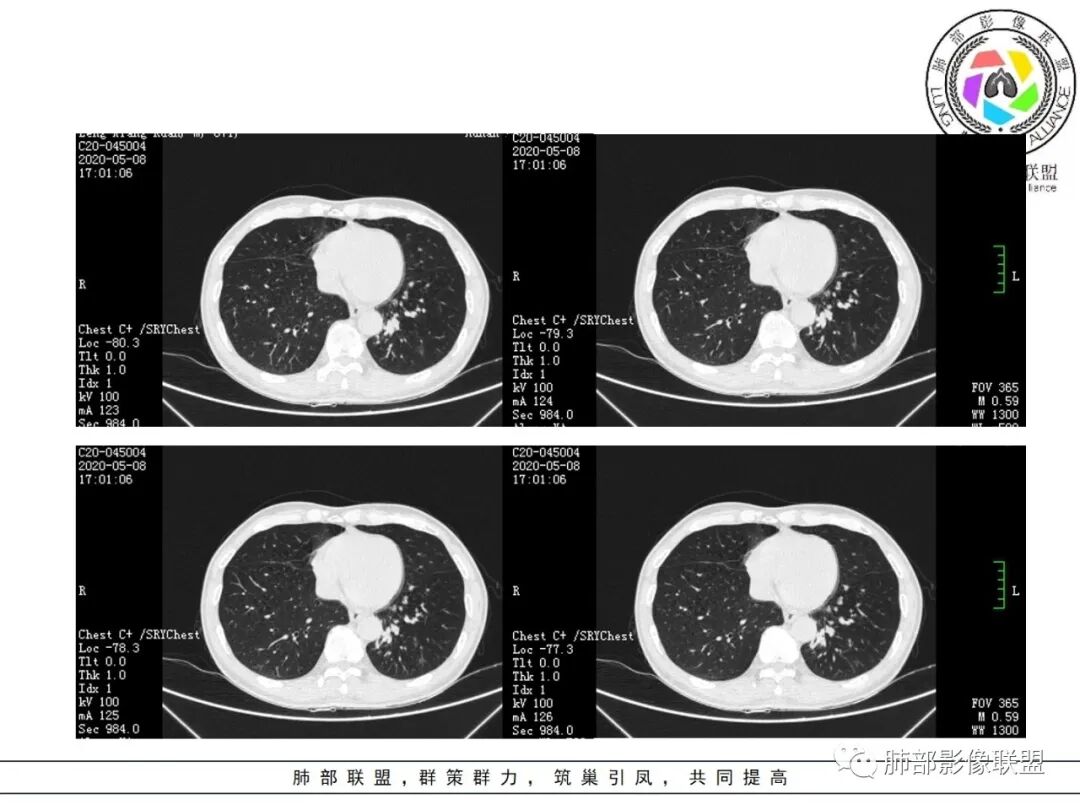

结节伴分叶。

斑片影,考虑阻塞性炎症。

支气管壁厚,支气管腔内高密度影填充。

周围散在斑片影及结节影,类似“小花花草草”的感觉。

2.关于支气管:上述病灶辖区外侧段支气管截断,环壁结节,远端阻塞性肺炎,是肺癌的重要征象。